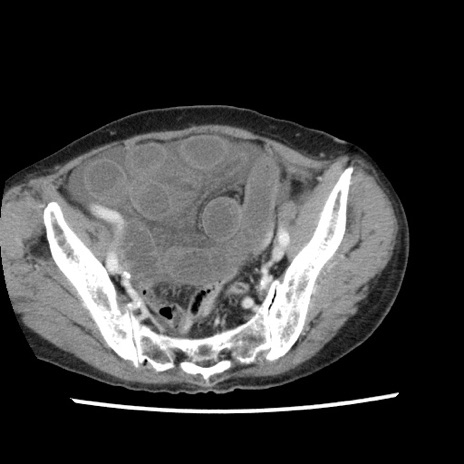

冠状断像

【症例】80歳代女性

【主訴】腹痛

【現病歴】8時間前から腹痛あり来院。

【既往歴】糖尿病、脂質異常症、子宮体癌にて子宮全摘術

【身体所見】意識清明・会話良好だが腹痛で苦悶様、全腹部にわたって反跳痛と圧痛あり

【データ】WBC 13600、CRP 0.14、LDH 224、CK 90